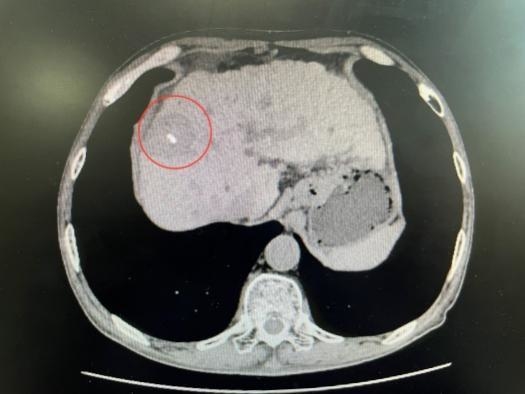

患者肿瘤紧贴膈肌

消融术中影像

患者消融术后2天复查病灶影像

消融术后2天复查结果显示,患者肿瘤已成功被灭活,膈肌功能正常,短时间内即可下床活动。据了解,“水隔离”辅助技术具备三大核心优势:一是安全性显著提升,将高风险手术转化为可控操作,杜绝严重并发症;二是实现肿瘤根治,打破“靠近关键脏器即消融禁区”的限制,治疗效果媲美外科手术切除;三是坚守微创理念,仅增加置管注冰水步骤,创伤小、恢复快。